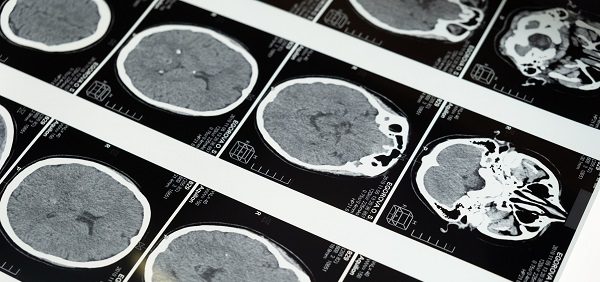

Przez ostatnie blisko trzy miliony lat ludzki mózg rósł szybciej niż u innych ssaków, dzięki czemu potroił swój rozmiar – aktualnie waży od 1300 do 1400 gramów. Duży mózg oznacza, że struktury odpowiadające za konkretne czynności mogą dzielić się na mniejsze jednostki, w których skupiska neuronów zmuszają mózg do specjalizacji i automatyzacji. Więcej neuronów wpływa na osobowość, pamięć, a nawet język i zachowania społeczne. Ludzki mózg, czyli najbardziej złożony narząd w ciele człowieka, wedle aktualnej wiedzy, nie posiada żadnych nowych elementów w porównaniu z mózgiem małp człekokształtnych; jego wyjątkowość stanowi nadzwyczajny rozwój niektórych jego regionów.

Na uwagę zasługują występujące w tych regionach neurony lustrzane, które uaktywniają się zarówno wtedy, gdy wykonujemy jakąś czynność, jak i w momencie kiedy patrzymy, gdy ktoś ją wykonuje. Sprawia to, że w przeciwieństwie do zwierząt możemy domyślać się, co dana osoba planuje zrobić; jesteśmy w stanie wczuć się w jej zachowanie i snuć w wyobraźni wnioski, co może spowodować dana

czynność.

Świadomość człowieka wynika z rozwiniętej znacznie bardziej niż u innych zwierząt tzw. kory nowej w mózgu, która u naczelnych rozrastała się w toku ewolucji nierównomiernie w stosunku do powiększania się mózgu, a obszary przetwarzające informacje zmysłowe rosły wolniej od innych elementów. Dziś wiadomo, że ludzie mają aż czterokrotnie więcej wolnej przestrzeni w płacie czołowym niż większe małpy, a to właśnie ten obszar odpowiada za wszystko, co związane jest ze świadomością. To budowa mózgu daje człowiekowi poznać samego siebie, podczas gdy większość innych gatunków jest w stanie jedynie żyć daną chwilą, skupiając się zwłaszcza na aspektach koniecznych do przetrwania.